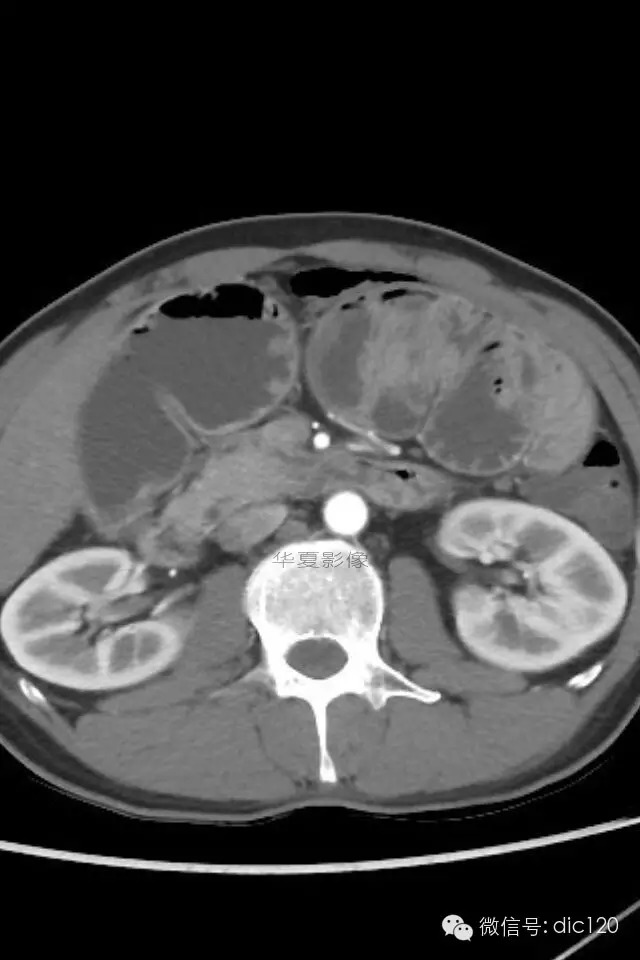

小肠禁锢症/腹茧症

肠茧症,即小肠茧状包裹症,又名:腹茧症,先天性小肠禁锢症。多为先天性畸形。

腹茧症以小肠被茧状包裹在一层异常的纤维膜内为其特征,为一种少见的,原因不明的特殊类型的肠梗阻。包膜厚薄不均,增厚处呈乳白色,包膜内小肠间或包膜间可有疏松粘连,包膜可局部增厚,形成缩窄环或束带压迫肠管形成梗阻,肠梗阻发生率约为57%,腹茧症伴腹腔内畸形率较高,约为54%。腹茧症92%的病人以肠梗阻就医,其中亚急性肠梗阻和慢性肠梗阻占71%,一些病人是在腹部手术时偶然发现本病。腹茧症女性多见,Francis总结以下情况可想到本病:1.青年女性,有不明原因的肠梗阻。2.既往又类似发作史,可自行缓解。3.常表现为腹痛及呕吐,但缺乏肠梗阻的四大典型症状。4.触诊腹部有无压痛的包块,质地软。腹茧症治疗以手术为主,充分松解粘连缩窄环,彻底解除梗阻使小肠复位或加以肠排列等。绝大多数病人术后症状消失,少数病人遗留症状,可试服用泼尼松,维生素B1治疗。

肠茧症分为两种类型:

1.单层包裹型 由单层纤维组织膜将小肠或其它脏器包裹。此种类型常包裹小肠及其系膜。手术时进腹容易,容易发生肠梗阻。

2.多层包裹型 俗称“千层饼”样包裹,其纤维层次多而广泛。手术时进腹困难,被包裹的脏器无移动性,发生肠梗阻的机会少。